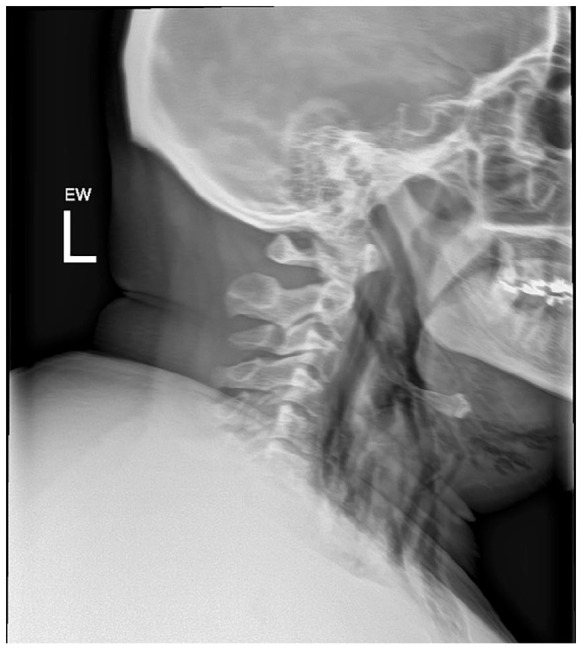

Spontaneous pneumomediastinum (SPM) is a rare, self-limiting condition that can be complicated by pneumothorax, pneumopericardium, and subcutaneous emphysema. This case describes a 25-year-old man with a chronic marijuana use history who developed SPM after a recent respiratory infection. Imaging showed significant pneumomediastinum, pneumopericardium, and small pneumothoraces bilaterally. Despite these findings, he remained stable and was treated conservatively with oxygen supplementation, analgesics, and close monitoring. By day 6, his condition had nearly resolved, and he was safely discharged. This case emphasizes the importance of considering SPM in young patients with acute respiratory distress and reinforces the value of computed tomography scans in promptly diagnosing and managing the condition without invasive interventions.